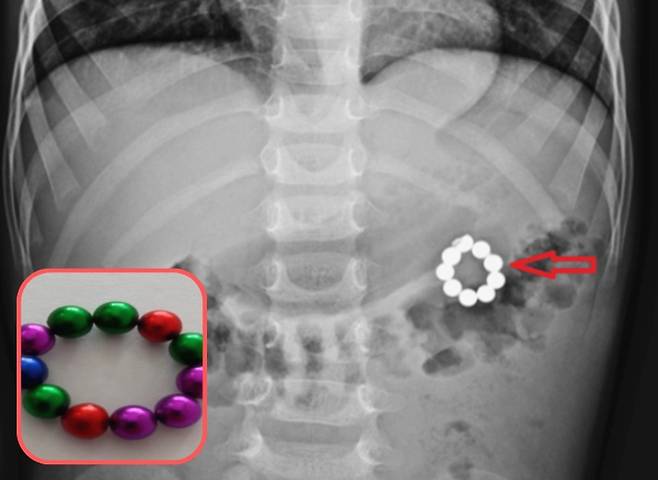

의료진에 따르면 5세 남아가 3일간 지속된 복통, 메스꺼움으로 병원을 찾았다. 복부 엑스레이 촬영 결과, 여러 개의 구슬이 연결된 모양의 이물질이 관찰됐다. 부모는 아이가 이물질을 먹는 걸 보지 못했지만, 장난감 상자에 비슷한 모양의 구슬 두 개가 있는 것을 발견한 뒤 체내 관찰되는 이물질이 자석 팔찌의 일부임을 확인했다.

의료진은 내시경으로 위 안에 있는 구슬 5개를 제거하는 데 성공했지만, 나머지 4개의 구슬은 제거하지 못해 응급 개복술을 시행했다.

개복술을 통해 직접 확인한 결과, 위와 대장을 잇는 비정상 통로인 위결장 누공이 형성돼 있었다. 의료진이 유착된 조직을 조심스럽게 박리해 두 장기를 분리하자, 이 누공 통로 안에서 자석들이 확인됐다. 통로 주변 조직은 두꺼워지고 염증과 경화(딱딱해지는 변화)가 진행된 상태였다. 의료진은 이를 자석의 장기간 압박으로 인한 만성 압박 괴사 때문이라 판단했다. 자석 구슬은 둥근 모양이었고, 각각 지름이 약 4mm였다. 아이는 나머지 자석을 제거하는 수술 후 6일째에 안정된 상태로 퇴원했다.